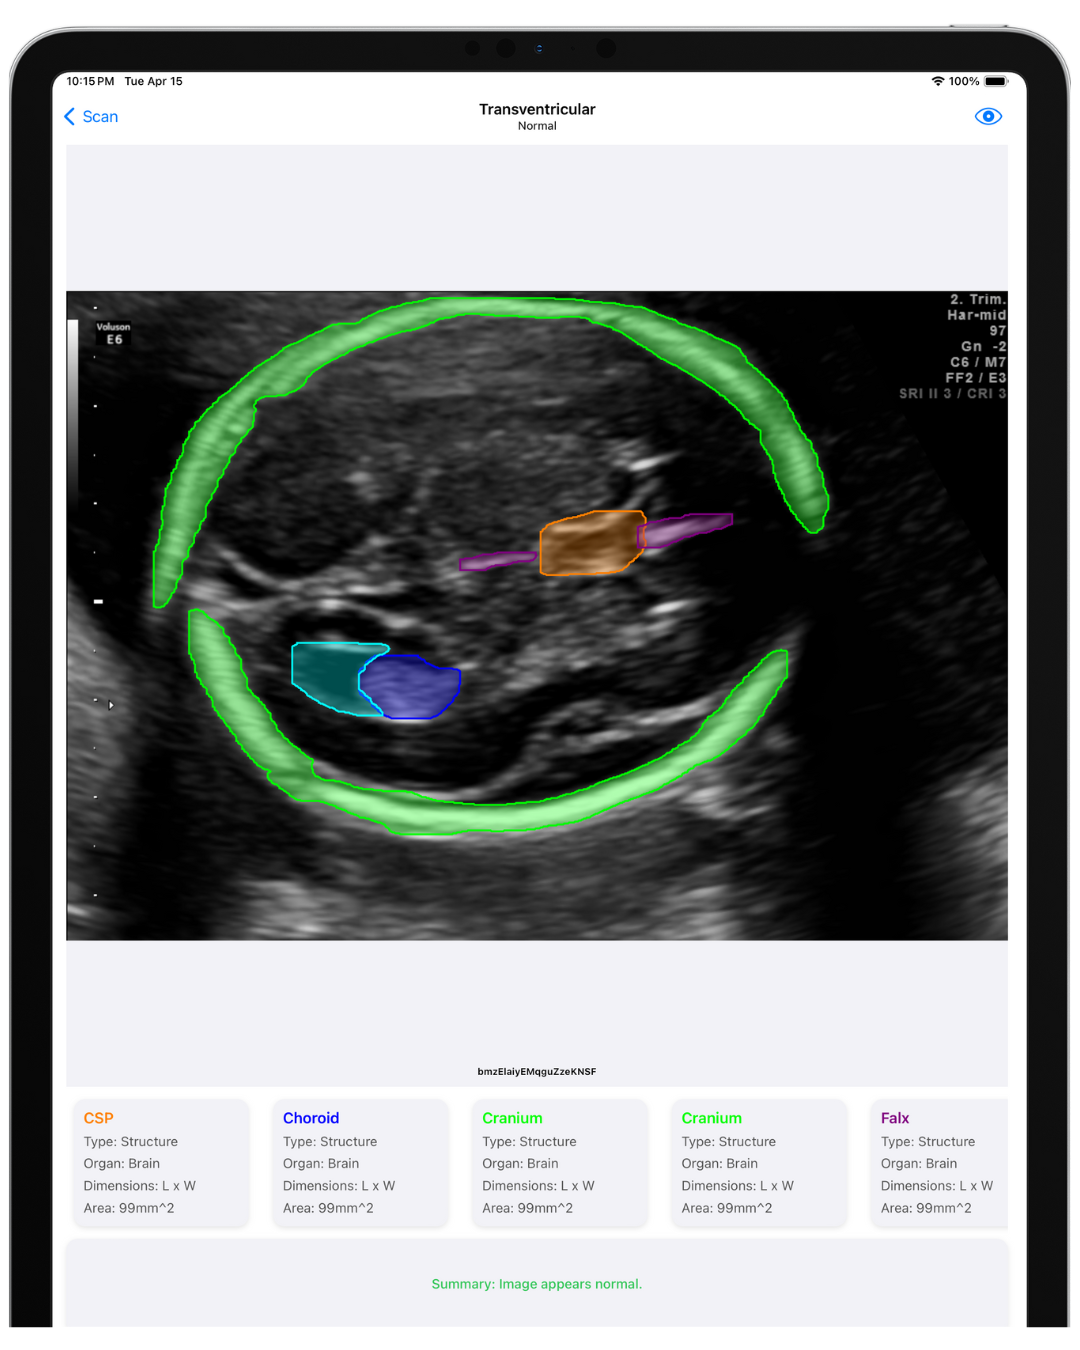

An AI platform to help physicians detect fetal anomalies and make confident decisions. Developed by Perinatologists and AI engineers for speed, accuracy, and cost-effectiveness.

See the platform in action